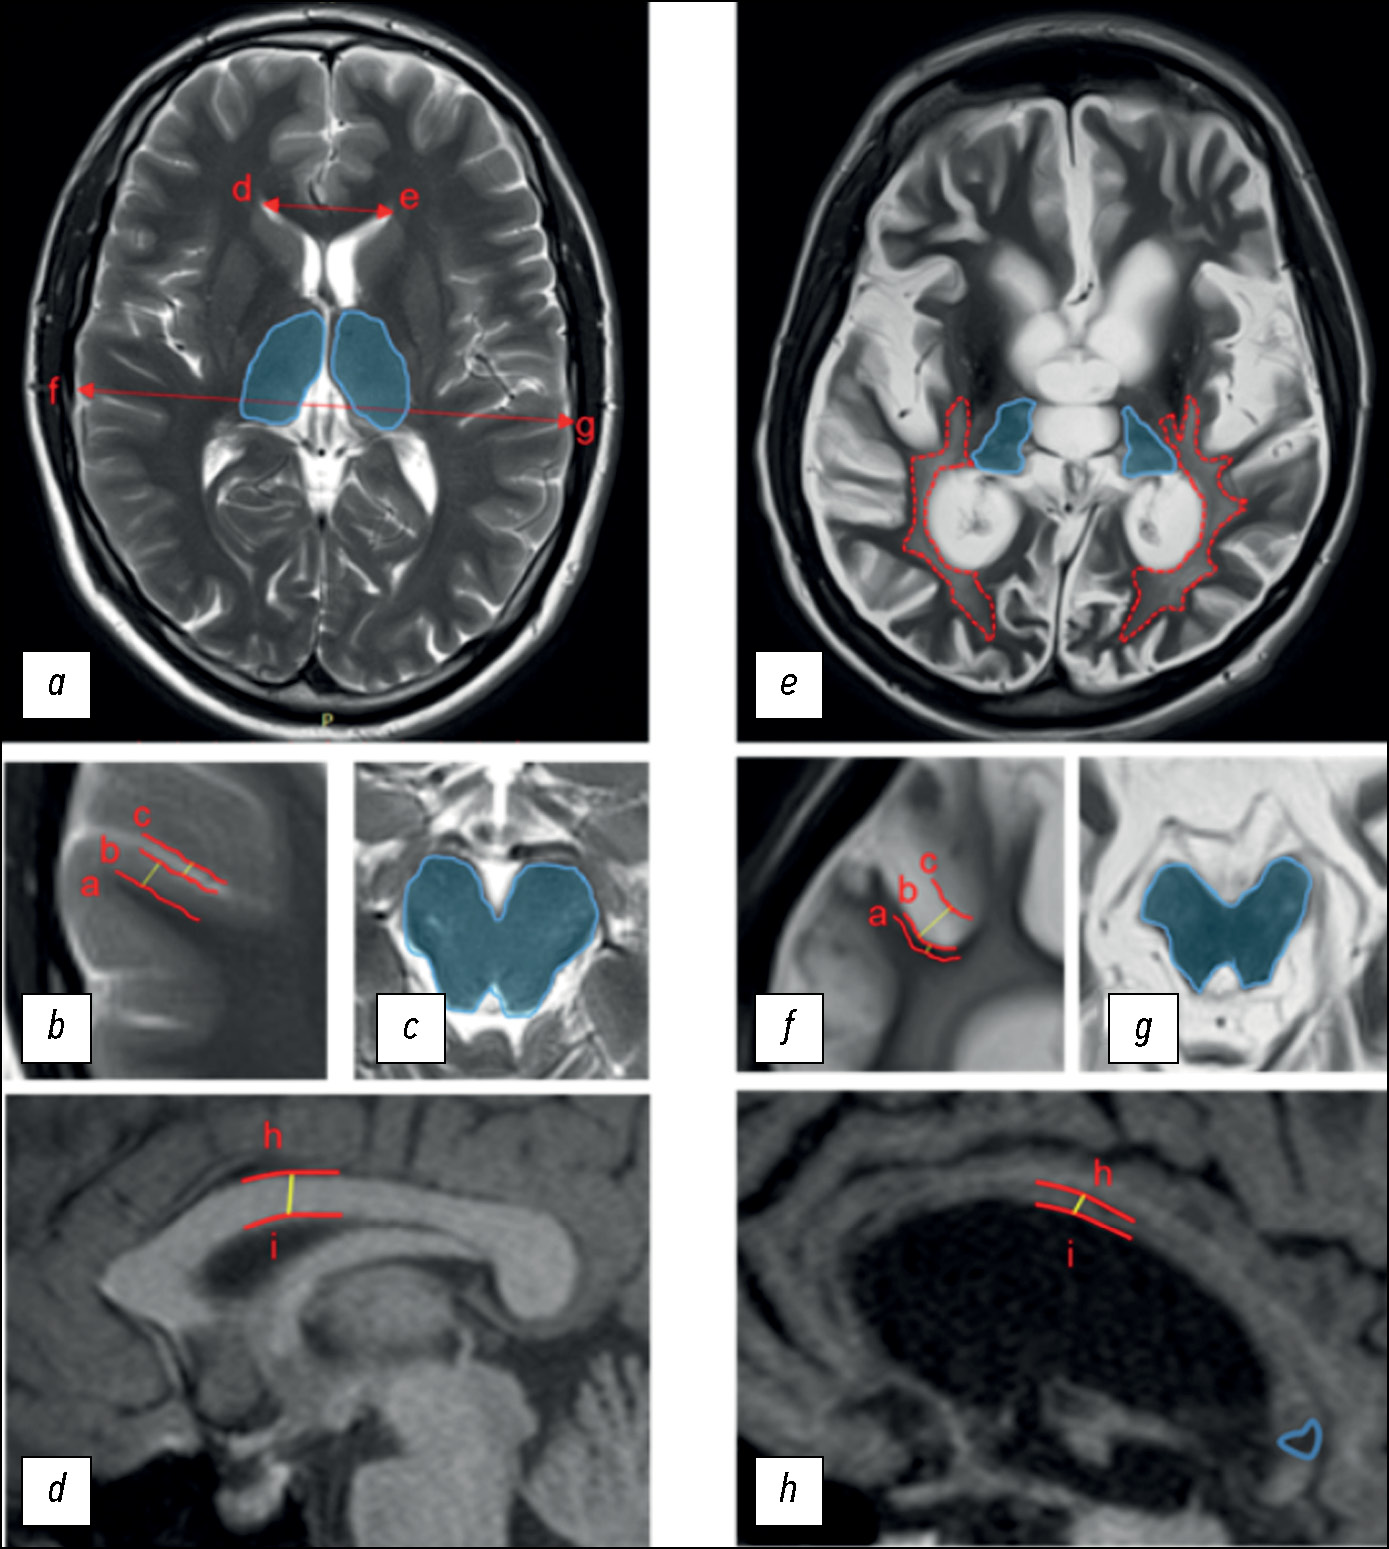

Conventional structural magnetic resonance imaging in differentiating chronic disorders of consciousness

AIM: To evaluate the inter-expert consistency and capacity of the researcher-developed structural scale based on magnetic resonance imaging to differentiate chronic disorders of consciousness, named, DOC-MRIDS, on a larger sample of patients.

MATERIALS AND METHODS: Sixty patients with a clinically stable status diagnosed with consciousness disorders (vegetative state, n=32; minimally conscious state, n=28) were enrolled. The revised coma recovery scale (CRS-R) was included in the clinical assessment. All patients underwent structural magnetic resonance imaging with 3.0-T Siemens scanners including T2 and T1 sequences. Structural changes were assessed using the DOC-MRIDS scale and included the following features: diffuse cortical atrophy, ventricular enlargement, gyri dilatation, leukoaraiosis, brainstem and/or thalamic degeneration, corpus callosum degeneration, and focal corpus callosum lesions. A total score was calculated. Magnetic resonance imaging data were analyzed by three neuroradiologists, and inter-observer agreement (Krippendorf’s alpha) was assessed.

RESULTS: A high inter-examiner agreement of the DOC-MRIDS scale score was found, with α=0.806 (95% confidence interval 0.757–0.849). The vegetative state group had a higher DOC-MRIDS score than the minimally conscious state group (p <0.005). A negative correlation was obtained between CRS-R and DOC-MRIDS scale scores (ρ=–0.457, p <0.0001), individual clinical scale domains, and magnetic resonance imaging features.

CONCLUSION: When assessing structural changes in patients with chronic consciousness disorders, the use of the DOC-MRIDS scale helps differentiate the type of such disorders with sufficient specificity, sensitivity, and inter-rater agreement. This scale can be used in clinical practice as an additional differential diagnostic tool.